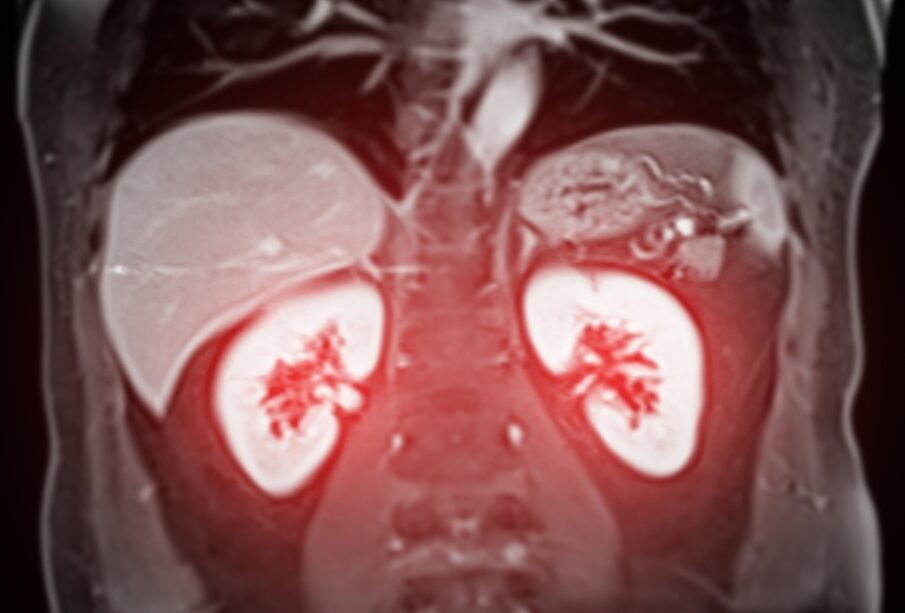

Ja pastāv aizdomas par nieru vēzi, ārstu komanda parasti izmanto vairāku izmeklējumu kombināciju, sākot ar ultrasonogrāfiju un turpinot ar datortomogrāfiju (DT) vai magnētiskās rezonanses izmeklējumu (MRI). Šīs metodes kopā ar asins un urīna analīzēm, rūpīgu pacienta apskati un iztaujāšanu palīdz ne tikai apstiprināt saslimšanas iespējamību, bet arī noteikt slimības stadiju un izstrādāt individuālu ārstēšanas plānu.

Attēldiagnostika: galvenās izmeklēšanas metodes

- Ultrasonogrāfija. Izmeklējumā ar skaņas viļņiem iegūst nieru attēlu; bieži tas ir pirmais solis diagnostikā. Metode palīdz atšķirt, vai atrastais veidojums, visticamāk, ir labdabīga cista vai blīvāks audzējam raksturīgs veidojums.

- Datortomogrāfija (DT). Nodrošina detalizētu informāciju par veidojuma izmēru un lokalizāciju, ļauj izvērtēt, vai process nav izplatījies ārpus nieres un vai nav skarti limfmezgli. DT var veikt ar kontrastvielu vai bez tās. Ja nieru funkcija ir traucēta, var izvēlēties alternatīvu izmeklēšanas metodi.

- Magnētiskās rezonanses izmeklējums (MRI). Īpaši noderīgs mīksto audu izvērtēšanā vai situācijās, kad pastāv aizdomas par audzēja izaugšanu vēnās. MRI var izmantot arī tad, ja pacientam ir kontrastvielas nepanesība vai nieru darbības traucējumi. Vienlaikus MRI netiek veikts, ja organismā ir metāla implanti.